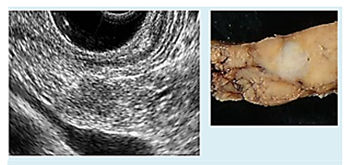

6.主な検査の有用性・超音波内視鏡

超音波内視鏡は内視鏡の先端に超音波装置があり、胃や十二指腸から膵臓を観察します。膵臓は胃や十二指腸に近接しているため、超音波画像で詳細で鮮明な膵臓の観察や膵臓がんの診断が可能です。

超音波内視鏡で診断した7㎜の膵臓がん/2006年 林香月ら